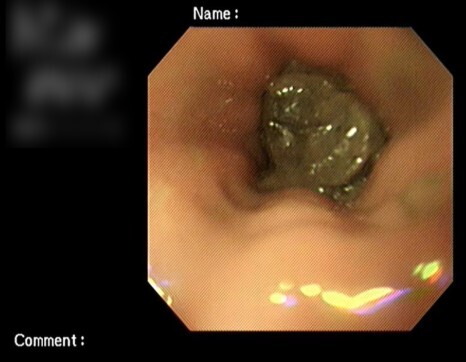

증상 때문에 다시 내원하였고 내시경으로 협착 부위

확인 후 풍선확장술을 진행하였습니다.